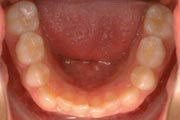

Crowding

Before